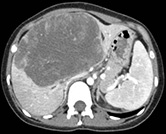

Undifferentiated Embryonal Sarcoma Submitted by Garrett Woodbury, University of Florida

27-year-old woman with right upper quadrant and epigastric pain with fullness in her upper abdomen.